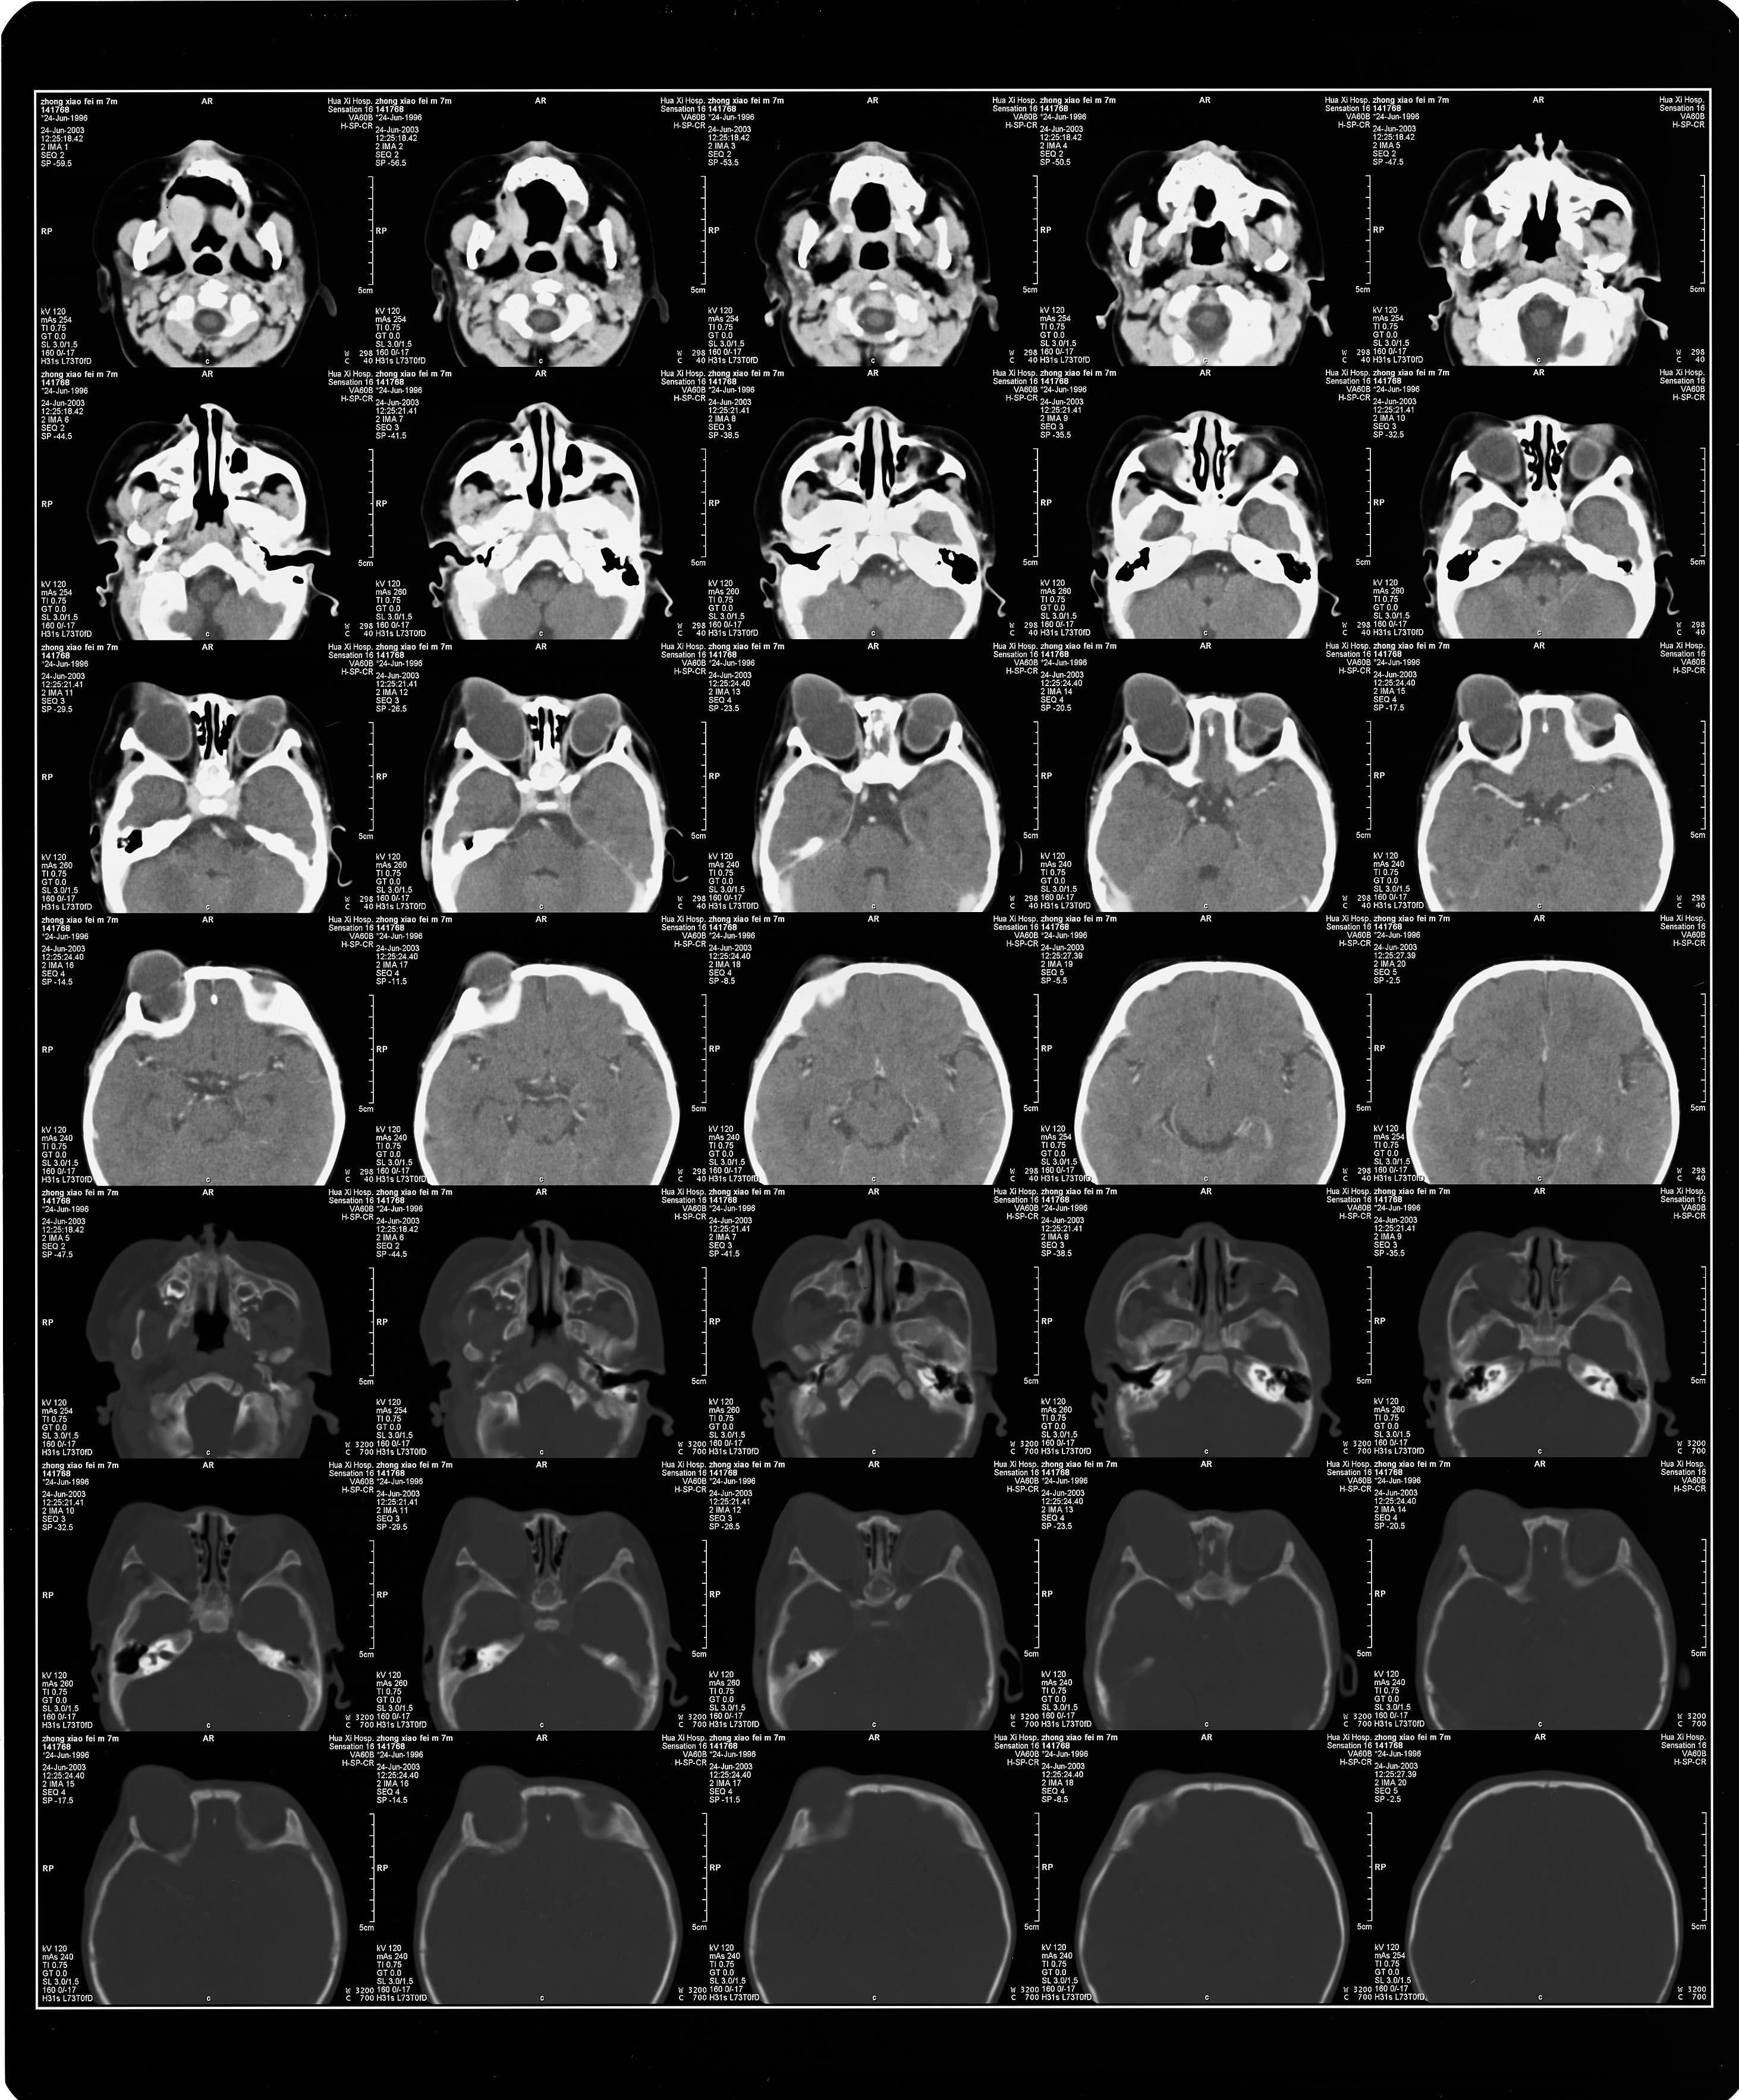

C  T:     双侧眼球增大,形态不规则,成分叶状,并向前突出.双眼晶体未显示,右眼视神经未显示.(见附图CT)

附上ct图片

附上图片